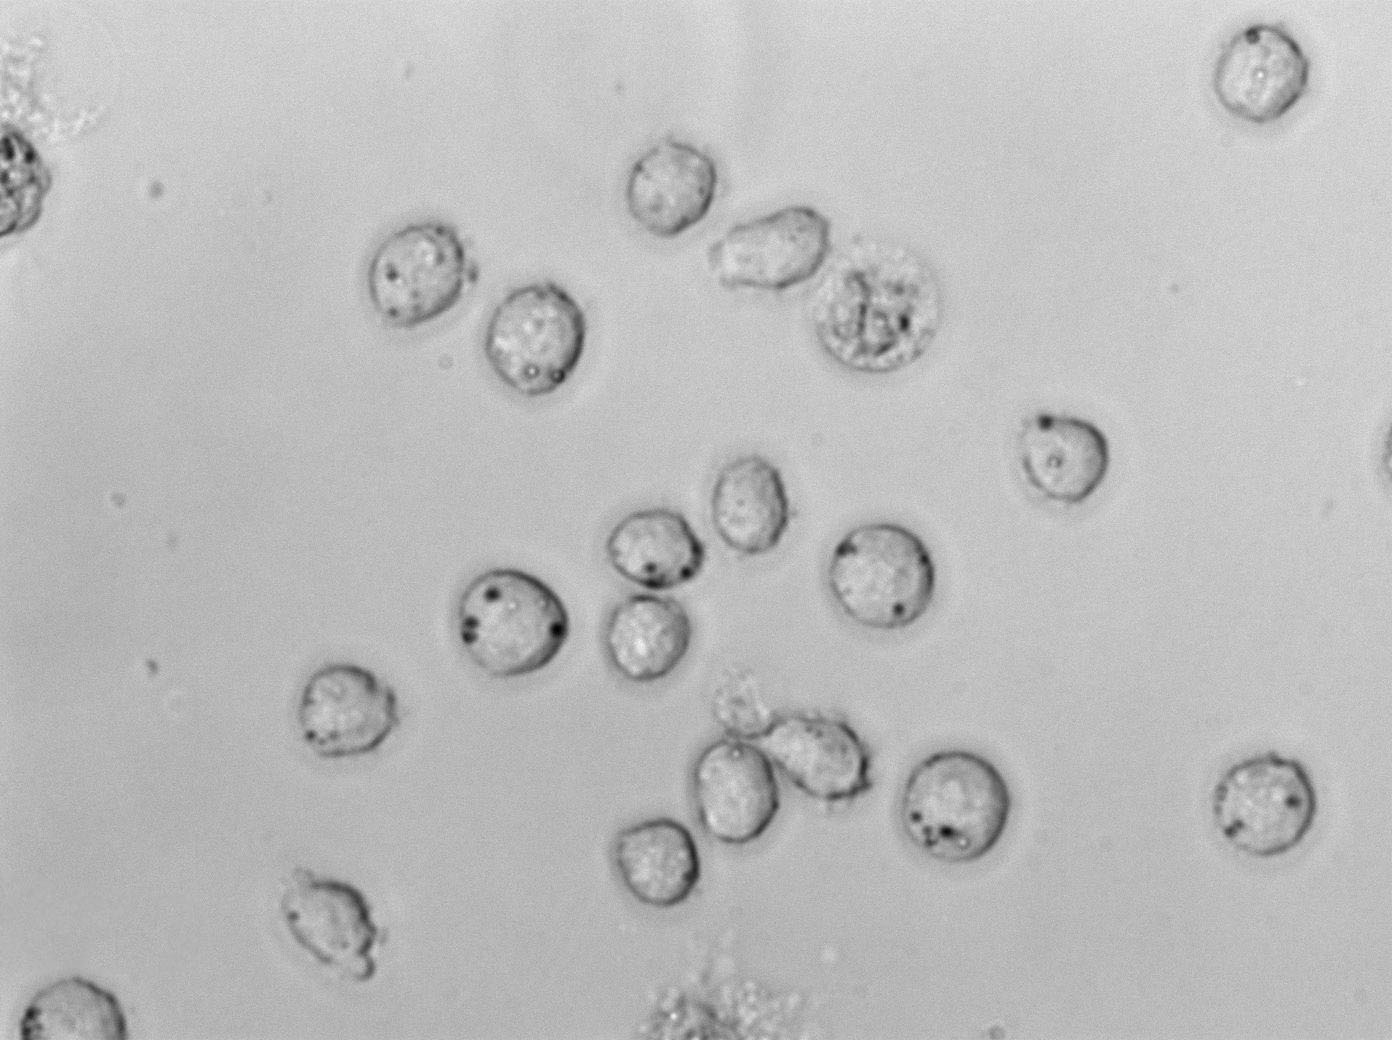

Mono-Mac-1:人急性单核细胞白血病复苏细胞(提供STR鉴定图谱)

细胞生长:悬浮

细胞背景资料:急性单核细胞白血病;男性

细胞形态:淋巴母细胞样

细胞生长特性:悬浮